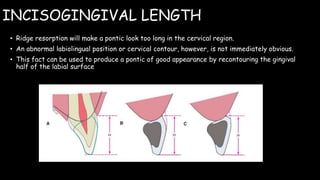

The document discusses pontic design for fixed dental prostheses. It covers pretreatment assessment of residual ridge contours, classifications of ridge deformities, surgical modification techniques, and ideal requirements for pontics. Pontic designs are classified based on their shape and materials. Factors in pontic selection include esthetics and oral hygiene. Common designs for anterior and posterior regions are described, including sanitary, ovate, and saddle pontics. Biological considerations for pontic design involve maintaining the residual ridge, abutment teeth, and supporting tissues.